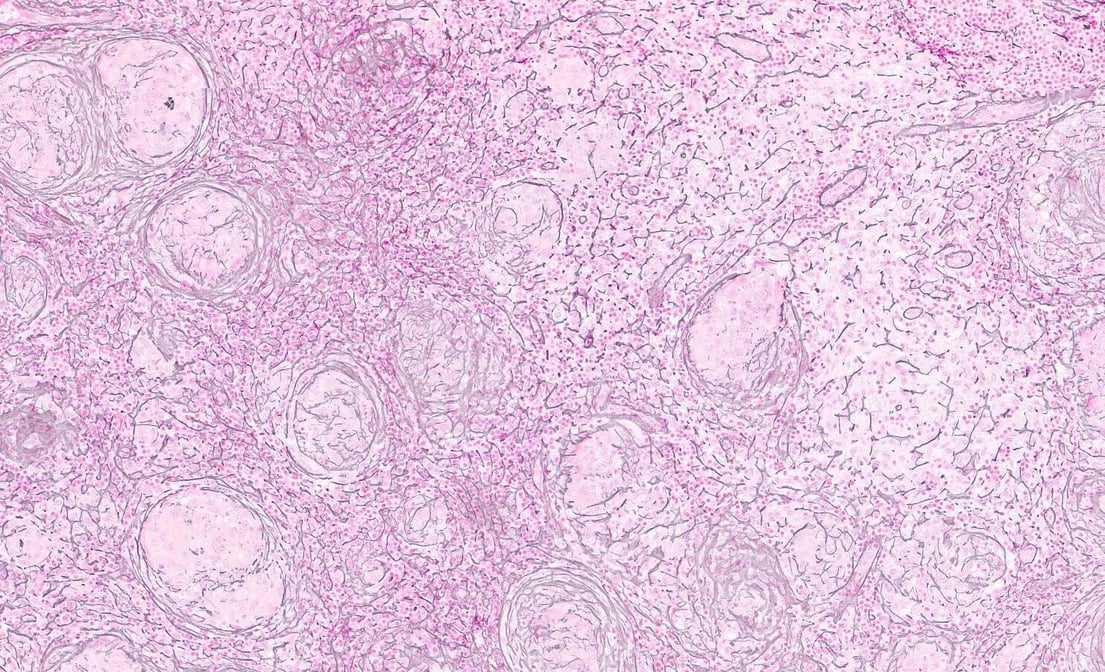

Reticulin Reticulin

Formalin-Fixed Paraffin Embedded (FFPE) Tissue

Extensive inventory of deeply-characterized, pathologist-reviewed FFPE tissue blocks, curls, and slides

FFPE tissue specimens are collected under IRB-approved protocols from high-caliber CLIA- and CAP-certified laboratories and hospitals in the US and our international partners and stored in our on-site climate-controlled biorepository. Our inventory contains a wide variety of disease and normal tissue, which undergo extensive pathologist review to ensure only the highest-quality samples are delivered to you. Precision’s network of partner hospitals and laboratories allow us to prospectively collect samples for indications not in our repository.

All of our FFPE tissue blocks that have undergone genomic characterization have matched H&E slide images that allow for pre-selection of your tissue blocks based on biomarker data, ensuring the samples selected have what you need. Whole slide images are available for all tissues upon request via Proscia Concentriq.